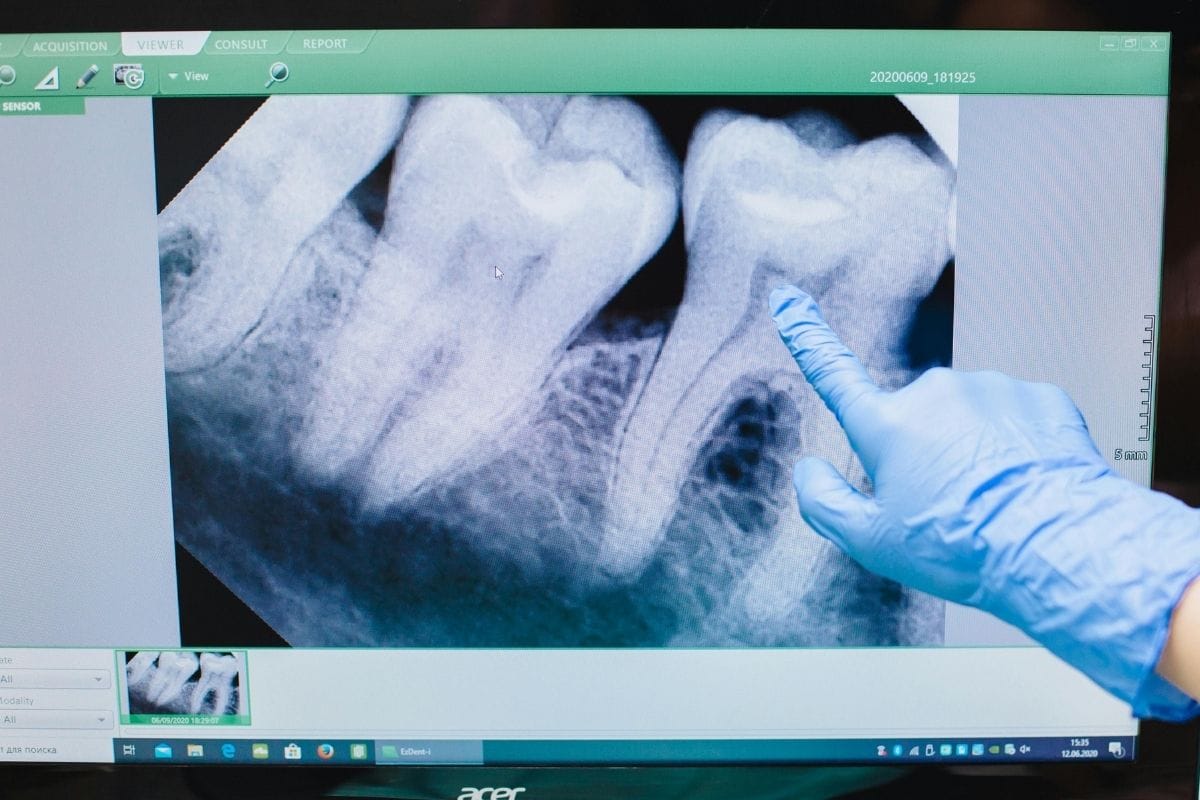

Diş çürükleri, kırıklar, travmalar ya da estetik nedenlerle zamanla yıpranan dişler, hastaların hem sağlık hem de görünüm açısından şikayetçi olduğu başlıca sorunlardandır. Restoratif diş tedavisi, çeşitli nedenlerle hasar görmüş diş dokusunun eski formuna kavuşturulması için uygulanan tedavi yöntemlerini kapsar.

Restoratif tedavide kullanılan yöntemler, dişin hasar durumuna ve ihtiyaç duyulan restorasyon türüné göre değişiklik gösterir: